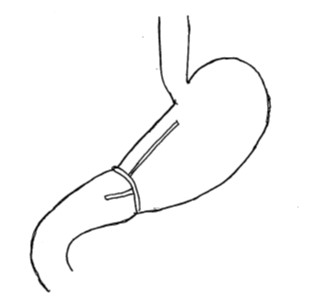

胃の入り口側半分を切除する術式です。胃の上部にできたがんや食道胃接合部癌などが適応になります。胃の入り口は噴門とよばれ、逆流防止弁の働きがあります。ここを含めて切除することになりますので、そのまま残った食道と胃をつなぐと胃液(胃酸)が食道へ逆流しひどい逆流性食道炎を起こすことになります。そのため、逆流を防止するような工夫をしたつなぎ方が必要となります。

<食道残胃吻合>

食道と胃を直接つなぐつなぎ方です。単純につなぐとひどい逆流性食道炎を起こすことになるため、逆流防止弁が作成されるようにつなぐ工夫が必要になります。また、このつなぎ方をするには胃が約3分の2程度残っているのが望ましく、残胃が小さくなる場合は次のダブルトラクト法が選択されます。